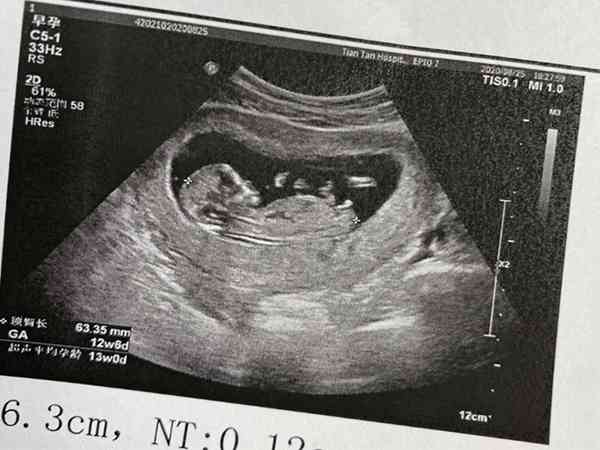

建档后的产假检查项目主要有三大类:一般检查(主要是询问孕妇的基本情况、分娩期推算、全身检查等等),产科检查(主要是测量子宫、胎心听诊、子宫和阴道检查等等),辅助检查(主要是抽血验尿、心电图、超声波等等)。而nt检查就包含在产检中的,如果说孕期错过了nt检查最佳时间,可以跟医生沟通后选择下一步是否要做这项检查,或者是做其他检查以保证孕妇在怀孕期间的身心健康。